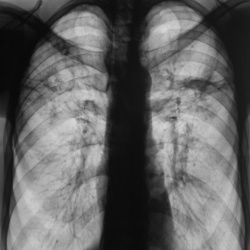

Интересная история со всевозможными реверансами.Зацепили по "флюшке"... Дообследовали по стандарту. Было высказано продположение о наличии специфического процесса. Была рекомендована...

18.04.2013 - 18:45